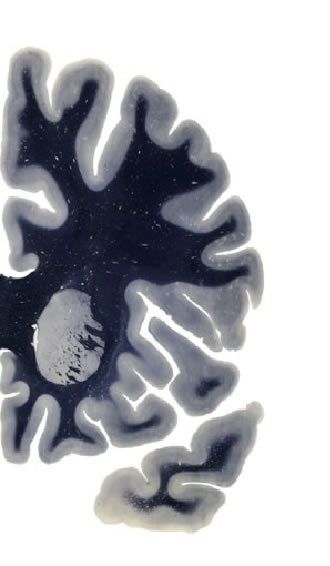

Hi-Resolution Sections · Cells (Nissl Staining) · Virtual Microscopy

Frontal sections (Nissl) from the Atlas Brain:

Slice ID:

r2-0500

Plate NR:

11

Position:

-17,5 mm